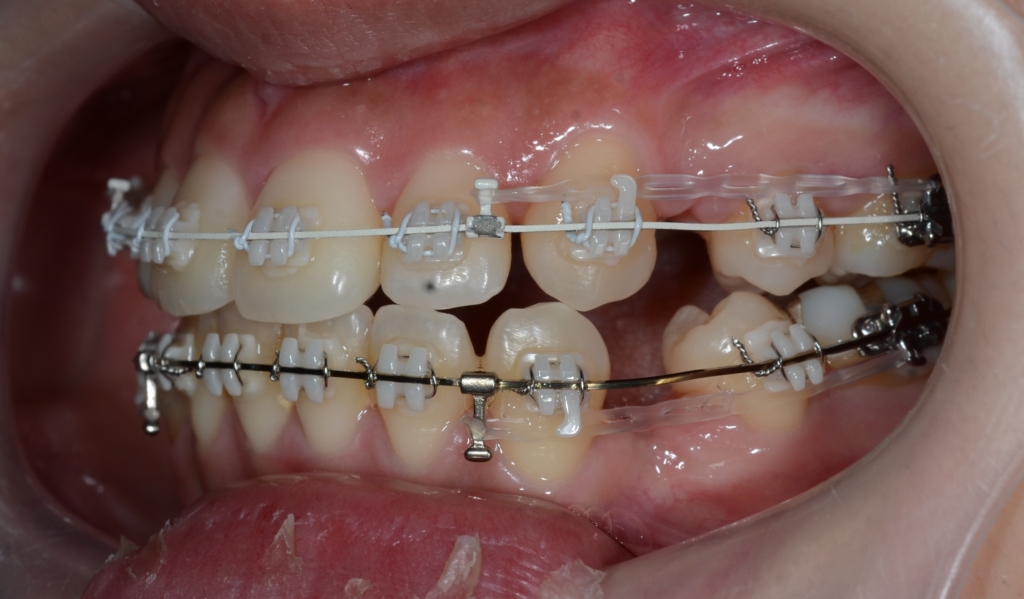

ついでに、歯並びの比較です

上段が矯正治療前、下段が矯正治療後